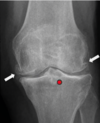

Classificação de Kellgren-Lawrence

Grau 3

Redução do espaço articular